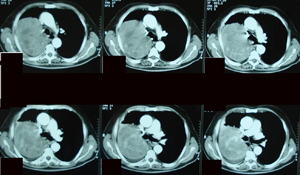

Εικόνα 3α-δ

Αξονική τομογραφία θώρακος σε διαφορετικά επίπεδα. Μάζα μαλακών μορίων που καταλαμβάνει το μεγαλύτερο μέρος του άνω λοβού. Η μάζα πιέζει την πνευμονική αρτηρία, τον κύριο βρόγχο και την άνω κοίλη φλέβα και πρόκειται για μάζα εκ μαλακών μορίων με νεκρώσεις κατά περιοχές.

Α-Β

Γ-Δ